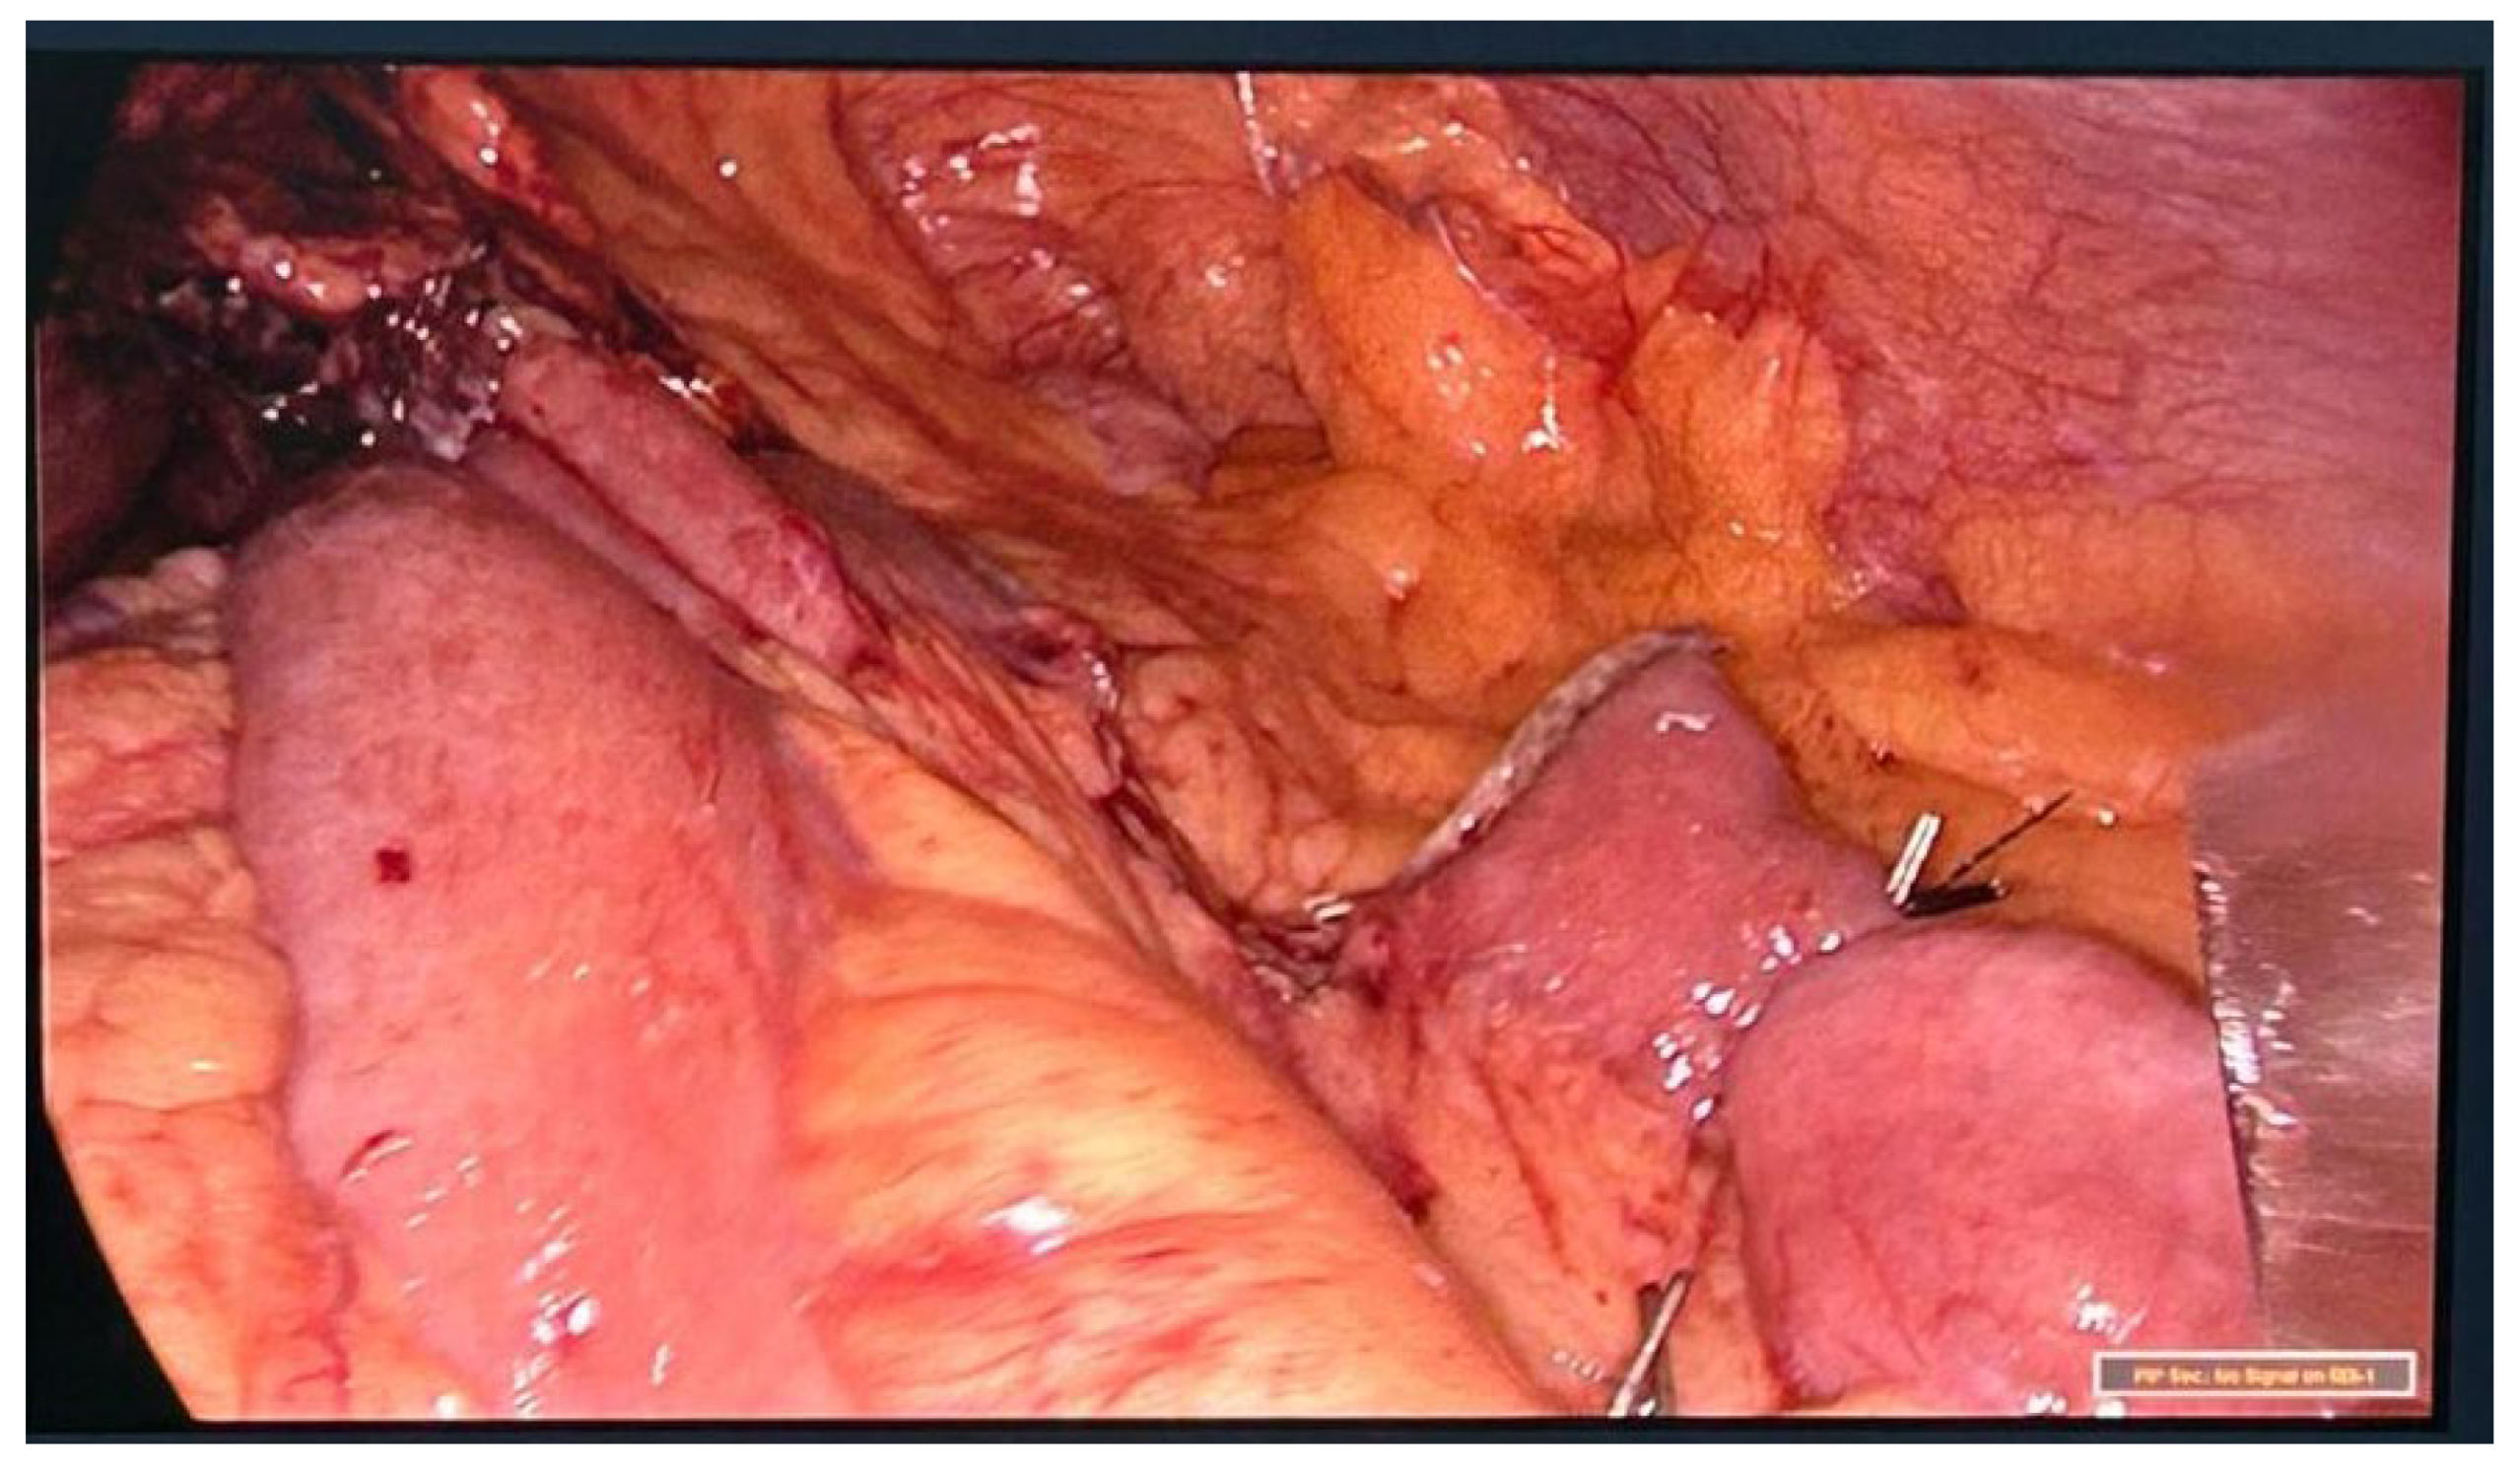

Patient arrives to the emergency room 48 hours after gastric sleeve surgery, she was admitted for abdominal pain referred to the left shoulder, a computer tomography (CT) was performed with evidence of leak at the gastroesophageal junction, a left subphrenic collection and pleural effusion of left predominance [Figure 1], she is taken to operation theatre and laparoscopic lavage and drainage is performed [Figure 2]. Treatment continues with IV antibiotics and parenteral nutrition. Thirteen days after re-intervention she presents deep venous thrombosis of the right lower limb and pulmonary thromboembolism of a segmental branch of the left lower lobe, she was managed with full anticoagulation and high flow cannula. She was then admitted to the intensive care unit (ICU) for 72 hours for observation. After stabilization is carried out, endoscopic management of the leak site with an Over-the-scope clip (OVESCO) is performed and mixed nutrition is installed, outpatient management is given with enteral nutrition for 4 weeks however the leak persists so after placement of vena cava filter, she is submitted for revisional Roux en Y gastric bypass [Figure 3]. Patient is discharged at 72 hours with complete resolution of the fistula, current follow-up at 4 months has been uneventful.

Figure 2. Intraoperative laparoscopy procedure showing gastrointestinal liquid contents in the abdominal cavity.